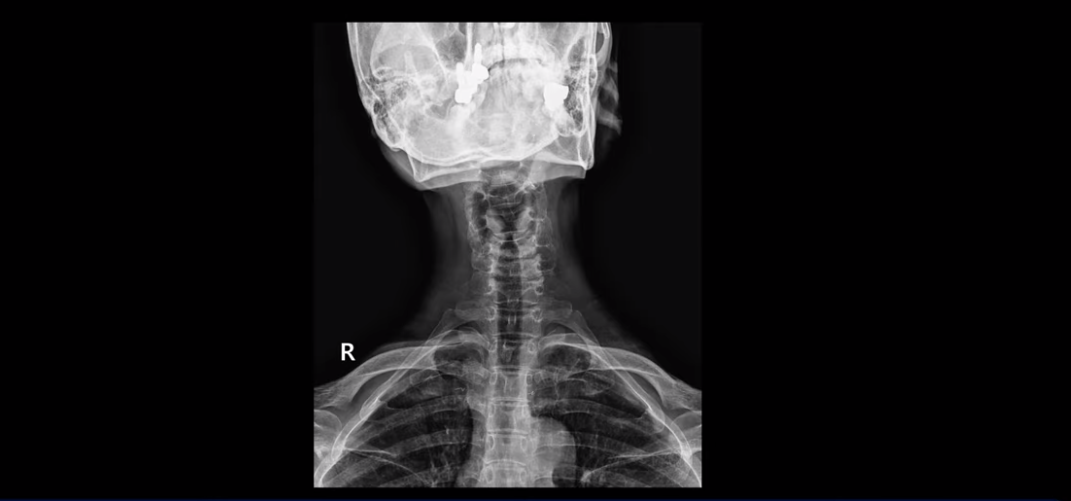

먼저 이분 MRI와 X-ray 보면서 간단히 설명해 드린 후 어떻게 목 협착증으로 신경이 눌려서 극심한 목통증과 견갑골 통증이 몇 달씩 지속되고, 고개가 조금도 돌아가지 않고 하루 24시간 아파서 잠도 잘 수 없는 환자가 수술 없이 비수술 치료로 좋아질 수 있는지, 치료는 어떻게 하는지 자세히 설명해 드리겠습니다. 참고로 이 환자분의 치료 후기는 2개입니다. 이분은 허리에도 심한 전방전위와 협착이 있어서 목 치료와 함께 허리 치료도 받으셨고, 허리 치료 후기 영상도 있으니 별도로 보시길 바랍니다.

목도 많이 휘어 보입니다.